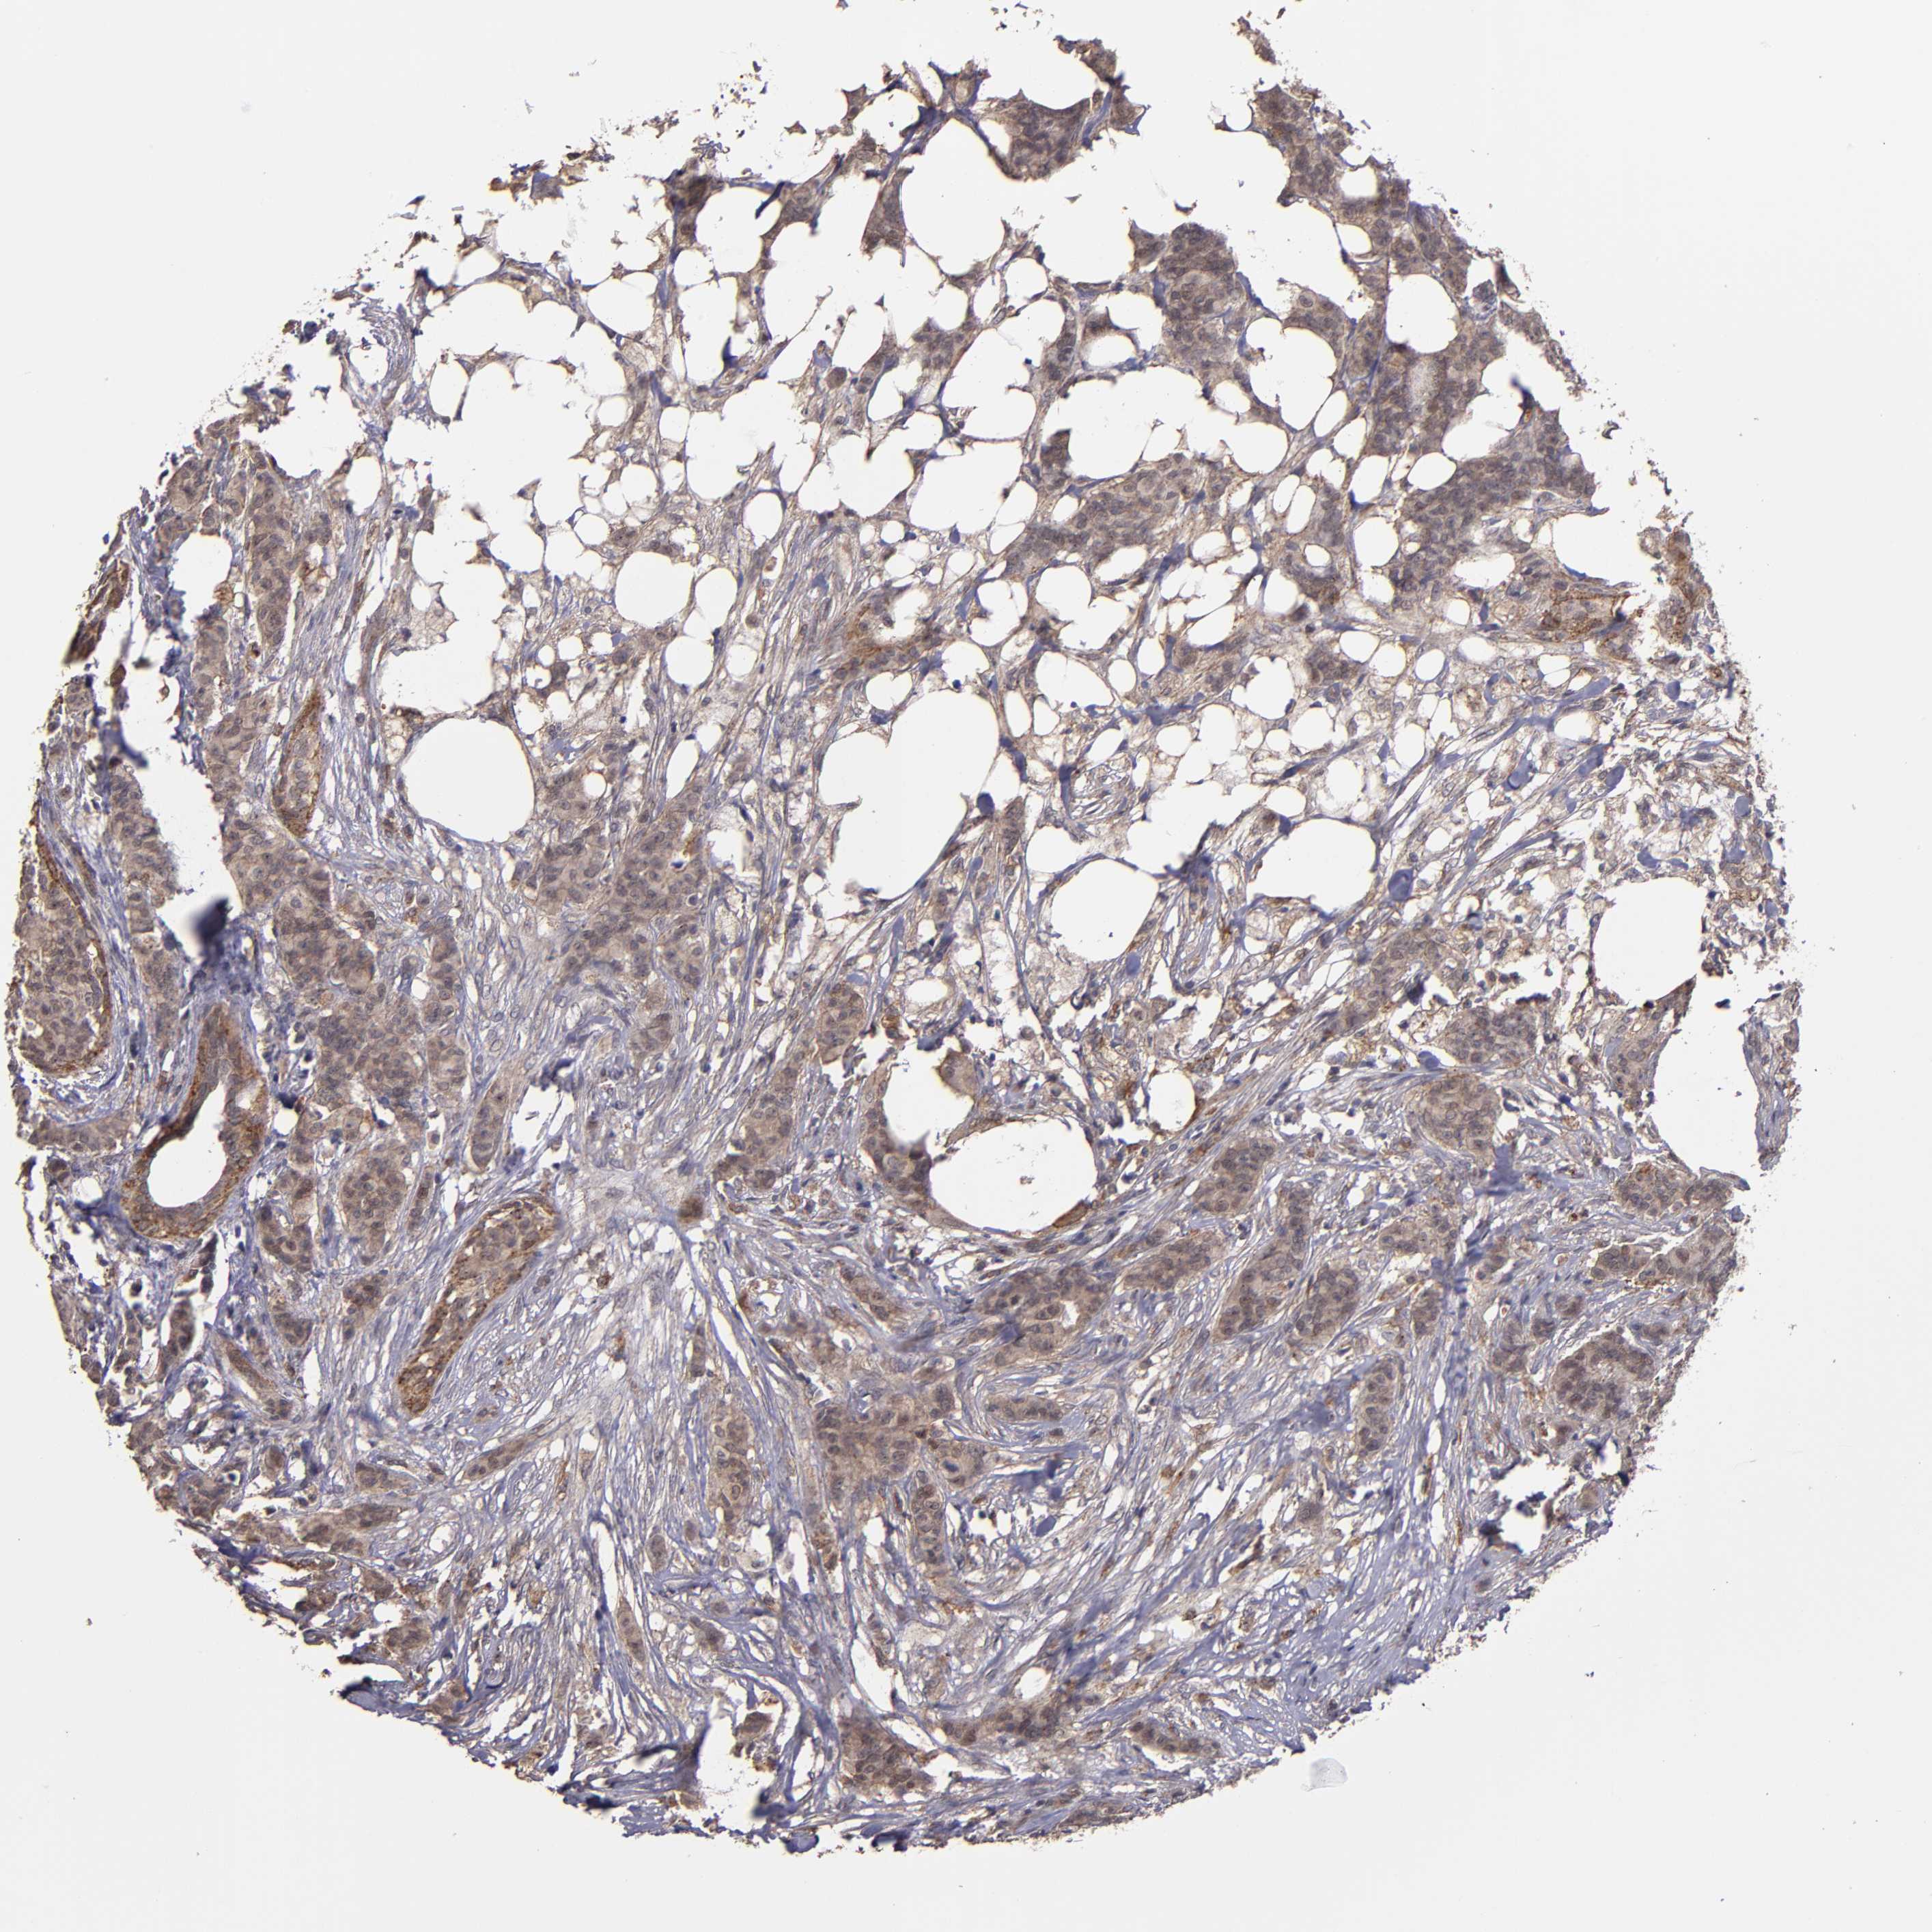

BRCA TCGA BRCA VALIDATION PROTEIN EXPRESSION

ANTIBODIES

AND

VALIDATION